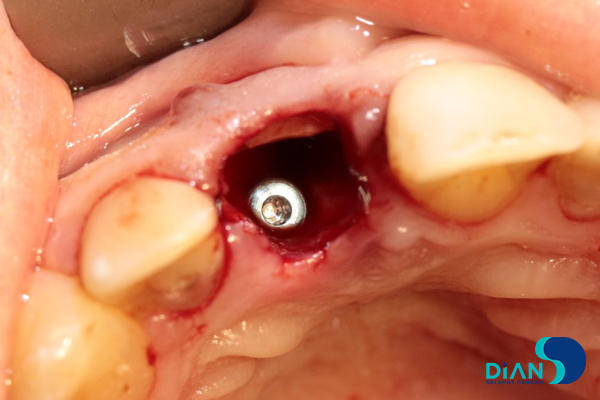

The alveolar socket was washed with antiseptic solution, and then the dentist made osteotomy while considering the future correct position of dental implant in the socket in relation to 12, 21 and 31 teeth.

He formed implant bed by following Bio3surgical protocols.

Bio3 implant Progressive 3.8/13 was entered from the box and fixed with 20-25 N/cm2 loading.

Cover screw was placed.

The gap between the implant and the tooth root was filled with bone material.